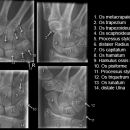

Handgelenk a.p.

Beurteilungskriterien

- Neigung der distalen Radiusgelenkfläche in der Frontalebene: 15 – 35°

- Längenverhältnis Radius – Ulna: Proc.styloideus radii überragt Gelenkfläche der Ulna um 9 –12mm (<9mm Ulna-Plusvariante, >12mm Ulnaminusvariante)

- Kontinuität der drei Karpalbögen:

Proximaler Bogen: proximale Gelenkflächenkonturen von Scaphoid, Lunatum und Triquetum

Mittlerer Bogen: distale Gelenkflächenkonturen von Sacphoid, Lunatum und Triquetum

Distaler Bogen: proximale Gelenkflächenkonturen von Capitatum und Hamatum

Fehlende Abgrenzbarkeit, Versatz oder Unterbrechung sind als pathologisch zu bewerten und deuten auf eine Luxation hin.

Trapezförmige Darstellung des Lunatum in Neutralstellung? Augenzeichen des Hamulus? Superposition von Pisiforme und Triquetum? Metacarpale III in Projektion innerhalb der Radiusgelenkfläche? Lunatum zu >50% über Radiusgelenkfläche? Cave: bei Radial- oder Ulnarduktion wandert das Lunatum in umgekehrter Richtung.

- M-förmiger Verlauf der Gelenkspalten der Carpometacarpalgelenke? Luxationsstellung in den Carpometacarpalgelenken (meist dorsale Luxation)?

- Gelenkspaltweiten des Radiocarpalgelenk 2 – 2,5mm, der Carpometacarpalgelenke 1 –2mm, distales Radioulnargelenk 2mm, Gelenksspaltweiten der Intercarpalgelenke 1,5 – 2mm

Cave: SL-Dissoziation (Ruptur des SL- Bandes, häufigste Gefügestörung): Terry-Thomas-Sign = SL-Spalt > 3mm, Siegelringzeichen = Ringförmige Transparenzminderung im mittleren Scaphoiddrittel durch orthograde Projektion der Taille infolge Rotation.

- Obliteration des Scaphoidfettstreifens?

- Täuschungsmöglichkeiten durch Vielzahl akzessorischer Ossikel (abgerundete, zirkulkär-geschlossene Kortikalis), geteilte Handwurzelknochen (Scaphoid, Lunatum, Pisiforme) und Gefäßkanälchen

- Target areas leicht zu übersehender Frakturen: distales Radioulnargelenk, Processus styloideus radii et ulnae, Basen der Metacarpalia (v.a. MCP I), Hamulus.

- Grundsätzlich gilt: unklare Verhältnisse ->CT-Indikation